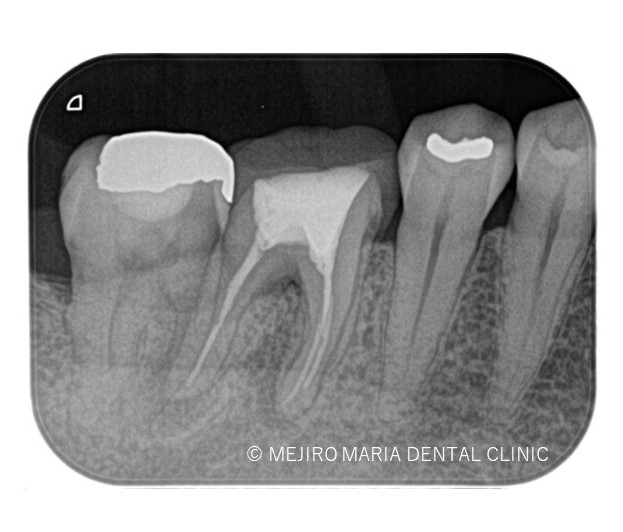

※画像は術前レントゲン写真と口腔内写真

5年前に治療した歯に違和感を感じることを主訴に来院される。当該歯は1年前に大きく腫れた時を境に徐々に調子が悪くなっているとのこと。

右の口腔内写真赤矢印部分には限局的な歯周ポケット10mmを確認し、歯根破折の可能性を疑わせる。